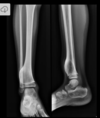

Fratura do platô tibial lateral - Schatzker tipo 2 (traço de fratura + depressão do plato lateral).